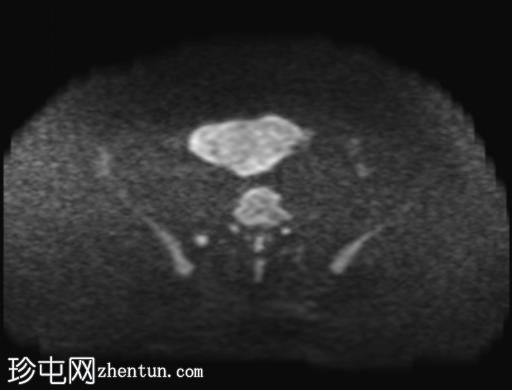

轴位

DWI

ADC

盆腔内可见多个边界清晰的肿块:

其中一个位于子宫上方,T2加权像呈中等信号,中心区域呈高信号,增强T1脂肪抑制像未见强化。右侧卵巢增大,增厚的血管蒂扭曲,未见强化,轴位和矢状位T2加权像均显示清晰。

另一个位于子宫后窝,T2加权像呈中等信号,增强扫描显示明显强化。

2个月前进行的MRI检查显示双侧卵巢肿块均有强化,右侧卵巢肿块未见扭转。